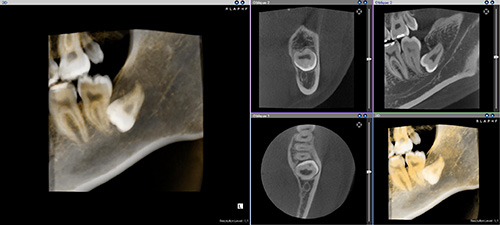

CTレントゲンの導入により、

3次元的な画像や骨や歯の形態を立体的に見る事が可能になりました。

歯科用CTの利点は、

歯科用レントゲンによって、今まで見ることができなかった骨や歯の状態を見ることができるようになりました。

大きな手術(埋伏抜歯(親知らず)・インプラント手術)はもちろんのこと、

小さなむし歯に対しても非常に有効です。

骨の中に人工歯根(インプラント)を埋め込むインプラント治療を行際、

安全かつ予後良好な治療を行ためには、骨の形(高さや厚み)

骨の中の神経や血管の位置を把握することは必須です。

歯科用CTで撮影することで、

埋入する部位の術前の骨の状態(質や厚み、高さ、形態など)が診断できるので、

安全に手術を行ことができます。

歯科用CTでの撮影画像をもとに、治療計画を立てることは、安心な治療への第一歩です。